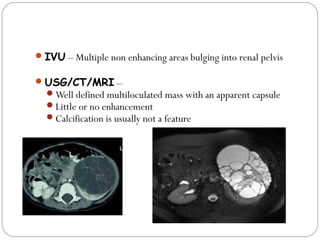

IVU – Multiple non enhancing areas bulging into renal pelvis

USG/CT/MRI –

Well defined multiloculated mass with an apparent capsule

Little or no enhancement

Calcification is usually not a feature